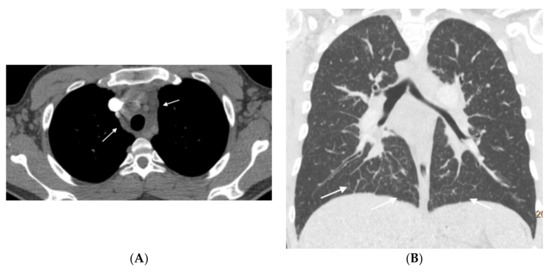

Figure 3.

Fifteen-year-old male with hereditary PVOD and three typical findings of PVOD in MDCT. Radiological signs of pulmonary hypertension: (A) Dilation of the pulmonary artery (PA) trunk and (B) Dilation of the right heart chambers with RV/LV ratio >0.9, hypertrophy of the right ventricular wall, and inversion of the interventricular septum; (C) Extensive involvement in centrilobular nodular ground glass (arrow) and septal lines (curved arrow). Mediastinal lymphadenopathy in subcarinal and bilateral hilar locations (arrows in (A)). PA: pulmonary artery. RA: right atrium. RV: right ventricle.